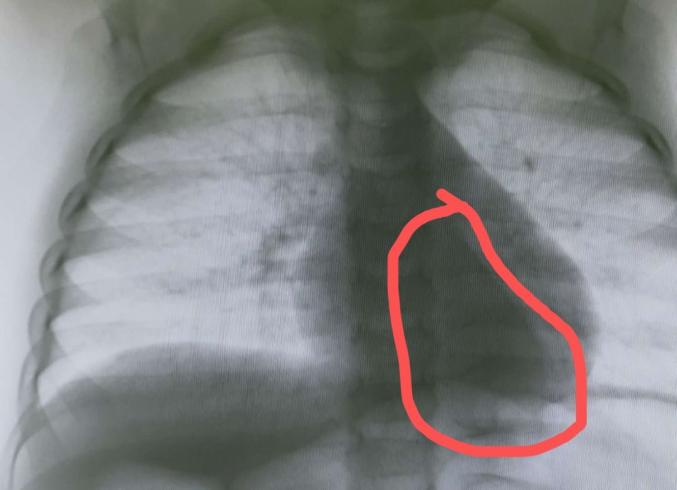

图中红色圈圈内就是心脏后面的肿瘤

儿童肠镜检查我们需要麻醉,麻醉之前我们这里常规需要常规拍个胸片,了解下心肺情况,有没有肺炎等影响麻醉的问题。胸片发现脊柱旁有个巨大肿块,考虑“神经源性肿瘤”,左侧的肋骨已经被肿瘤破坏了,由于炎症渗出左侧胸腔出现积液。